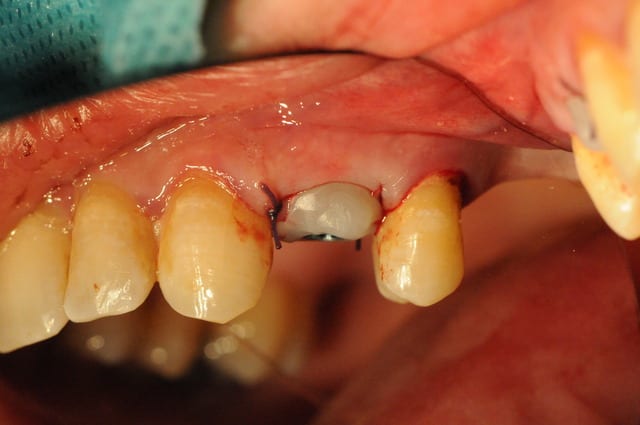

Tiens pour agrémenter! Cet Après midi une extraction implantation. Je n'ai pas oser la mise en charge immédiate si certains l'aurait fait lachez vous.

J'ai fait sauter la table vestibulaire exprès car je ne vois pas comment elle aurait pu etre vascularisée et à part me faire un séquestre osseux et des ennuis j'ai reconstruis.

Regardez les images;

Si certains n'auraient pas extrait argumentez pour traiter en palatin et la felure englobé par le granulome m^me si ce n'est pas mis en évidence sur le scan.

En plus vous voyez le nouvel implant Leone et son indication majeure, c'est vrai que sa mise en place est super aisée, surtout comme celà en palatin.